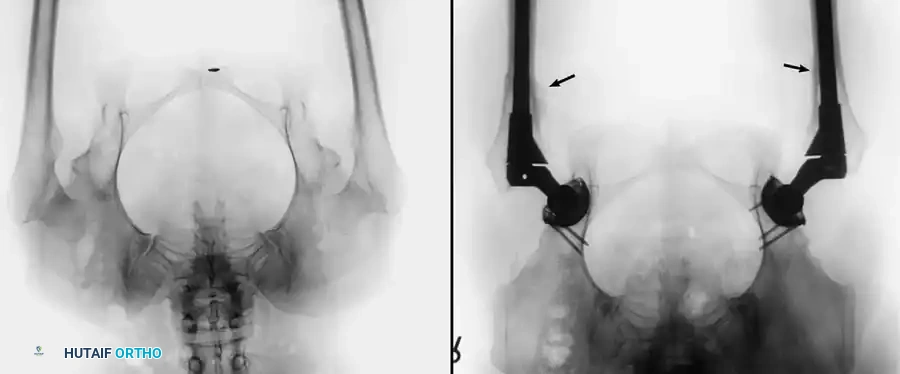

PROTRUSIO ACETABULI

Intrapelvic protrusio acetabuli is defined radiographically by the medial migration of the femoral head beyond the ilioischial (Kohler) line.

Fig. 7-74 Primary protrusio acetabuli. Otto pelvis in 52-year-old woman. Femoral head has migrated medial to ilioischial (Kohler) line. Hip motion is severely limited.

Principles of Reconstruction

The surgical management of protrusio acetabuli is technically demanding and relies on three non-negotiable biomechanical principles:

1. Restoration of the Anatomic Hip Center: The hip center of rotation must be lateralized and brought inferiorly to its true anatomic position to restore abductor mechanics and minimize joint reactive forces.

2. Peripheral Rim Fixation: The implant must be supported by the intact, structurally sound peripheral rim of the acetabulum, bypassing the deficient medial wall.

3. Medial Wall Reconstruction: Cavitary and segmental defects of the medial wall must be reconstituted, typically utilizing impaction bone grafting (autograft from the resected femoral head or allograft).

Fig. 7-75 Reconstruction for protrusio acetabuli deformity. A, Diagrammatic representation of medial wall grafting and lateralized cup placement.

Fig. 7-75 Reconstruction for protrusio acetabuli deformity. B, After total hip arthroplasty. Hip center was restored to more lateral and inferior position. Large acetabular component allowed rim fixation without need for screws, and medial deficits were grafted with cancellous autograft from femoral head with excellent incorporation.